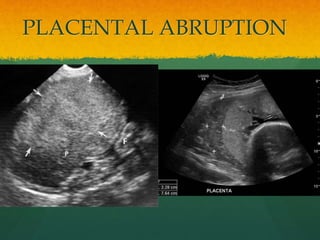

PLACENTAL ABRUPTION

 Premature separation of placenta from the

myometrium

 Secondary to hemmorrhage into decidua basalis

 20 wks to birth

 If >60 ml blood

loss chances of

SONOGRAPHIC SIGNS

OF ABRUPTION

 Diffuse placental thickness

 Retroplacental mass

 Rounded placental edge

 Separation of placental edge

 Intra-amniotic hemorrhage

 Preplacental or subamniotic mass

 Blood in the fetal stomach